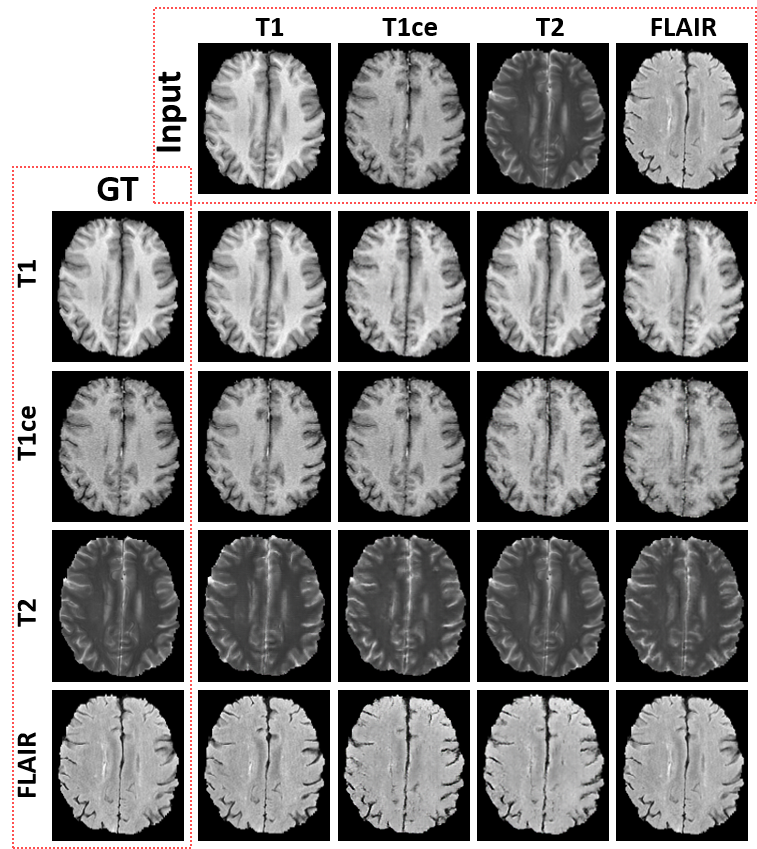

Refer to caption

Fig. 2: Illustration of the results of our proposed framework. We use the first row as input, and configure four target modalities. The diagonal results are obtained using self-translation (i.e., my=mxsubscript𝑚𝑦subscript𝑚𝑥m_{y}=m_{x}).

In Fig. 2, we illustrated the multimodal generation results of 12 cross-modality translation tasks and 4 self-reconstruction tasks. The proposed framework successfully synthesized any modality by simply configuring the target modality, which is consistent with the target ground truth MR images. We note the self-supervision was not used for the subsequent segmentation, but was used for checking the image generation quality in our implementation.